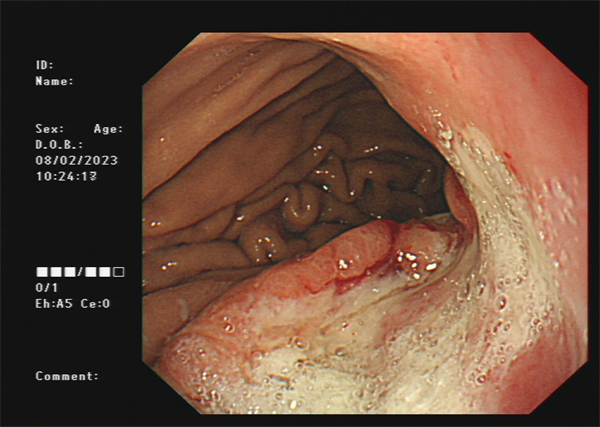

患者周某,男60岁,体检行肠镜发现直肠肿物,行肠镜下直肠黏膜下剥离术(ESD),术后病理:绒毛状管状腺瘤,局灶呈高级别上皮内瘤变。

· 食管、胃、结直肠早期癌粘膜下剥离术(ESD)